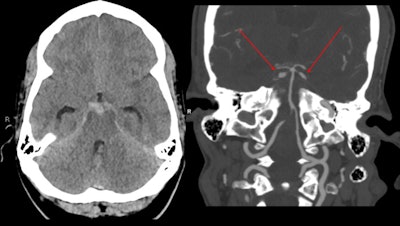

Cocaine-induced midline destructive lesion syndrome is a common complication of snorting cocaine, and about 5% of users will have a nasal septal perforation, the authors wrote. The lesion can progress to destroy the palate and nasal walls, producing a saddle-nose deformity, and eventually to necrosis of the midface.

"Cocaine causes cerebral vasospasm, and significantly reduces cerebral blood flow," they pointed out. "Cocaine abuse is also associated with both parenchymal and subarachnoid hemorrhage, which are twice as common as ischemic events."